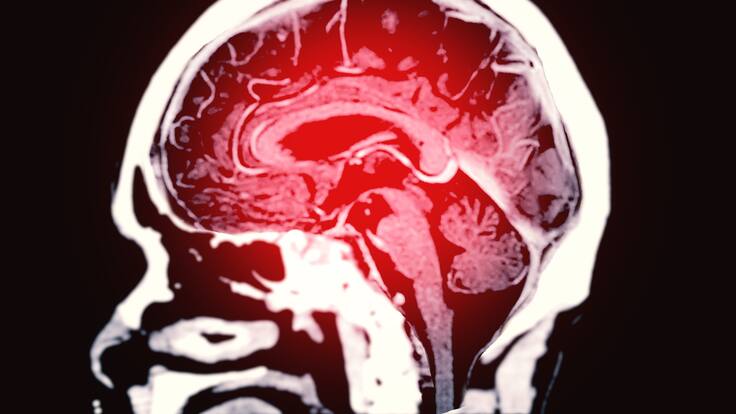

Los accidentes cerebrovasculares son una trombosis cerebral en donde se forma un trombo o se da una hemorragia de manera súbita.

Para empezar, el neurólogo explico que los accidentes cerebrovasculares son una trombosis cerebral en donde se forma un trombo o se da una hemorragia de manera súbita, presentando síntomas incapacitantes y posiblemente mortales.